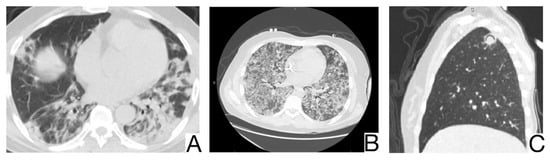

Yet, a discordance between the patients’ anamnesis and the imaging should suggest a possible differential diagnosis [,]. Comparison with previous CT scans is crucial to identify possible chronic or long-standing radiological findings of IIP. In general, the presence of typical and/or additional radiological changes that are less frequent or rare in COVID-19 pneumonia is found in IIP (Figure 13A,B) [,]: the migration of condensation foci (organizing pneumonia); preferential involvement of the lobular periphery, resulting in a “peri-lobular pattern” (pneumonia in organization); ground glass opacities during disease exacerbation; relative reduction of the subpleural lung tissue (nonspecific interstitial pneumonitis, organizing pneumonitis); predominance in the upper fields (bronchiolitis associated with interstitial lung disease, lymphoid interstitial pneumonia, pleuropulmonary fibroelastosis) []; apicobasal gradient and heterogeneous lung involvement (idiopathic pulmonary fibrosis); clear demarcation between the healthy lung parenchyma and the affected parenchyma (idiopathic pulmonary fibrosis) []; the coexistence of other radiological findings such as centrolobular nodules (bronchiolitis associated with interstitial lung disease, organizing pneumonia) and thin-walled cysts (interstitial lymphoid pneumonia) []; the presence of fibrosis that can be appreciated as parenchymal distortion, bronchial traction, and/or honeycombing (idiopathic pulmonary fibrosis, nonspecific interstitial pneumonitis); pleural thickening (pleuropulmonary fibroelastosis); pleural effusions (exudative acute interstitial pneumonia, organizing pneumonia).

Figure 13. Idiopathic interstitial pneumonia (A,B). Bilateral septal thickening and honeycombing with more severe involvement toward the lung bases. Note. Case courtesy of Dr. Hani Makky Al Salam, Radiopaedia.org, rID: 41974.